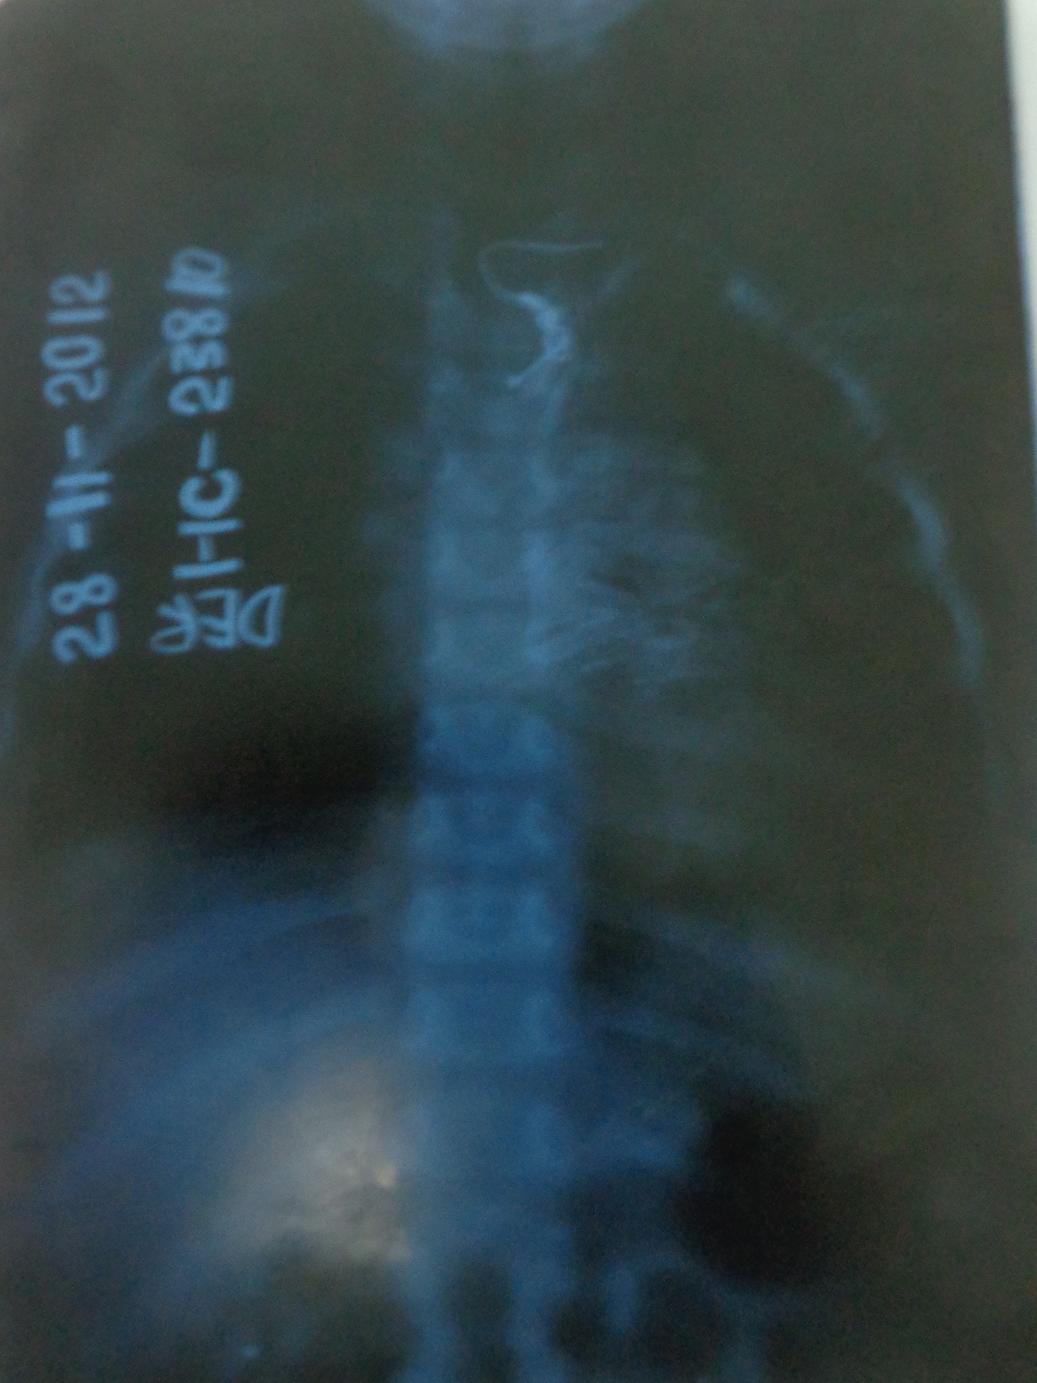

“En vías digestivas son posibles las perforaciones, las fístulas, la periesofagitis (inflamación del esófago) y en el caso de menores de un año podría traer consigo la muerte súbita por paro cardiorespiratorio.

“Pero el peligro mayor se concentra en los cuerpos extraños bronquiales con tres estadios básicos: cuando el paciente siente que se asfixia, hace un cuadro aparatoso de tos y se pone cianótico: ahí puede ser que fallezca ante la imposibilidad de respirar, o bien que expulse el objeto, o que desafortunadamente este vaya hacia uno de los bronquios.

“He ahí la etapa crítica, señala enfático el doctor Francisco Macías Fonseca, profesor auxiliar de Otorrinolaringología, la familia no puede pensar que llegó la calma y todo pasó, por el contrario, es ese el momento crucial, en el que con más premura hay que acudir al médico, principalmente si se trata de semillas: frijoles, maíz, maní, mamoncillo, tamarindo, anón…